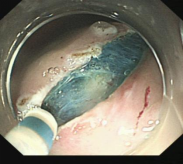

食管胃底静脉曲张内镜下套扎、组织胶治疗

肝硬化食管和胃底静脉曲张破裂出血的内镜下组织胶注射和套扎序惯治疗